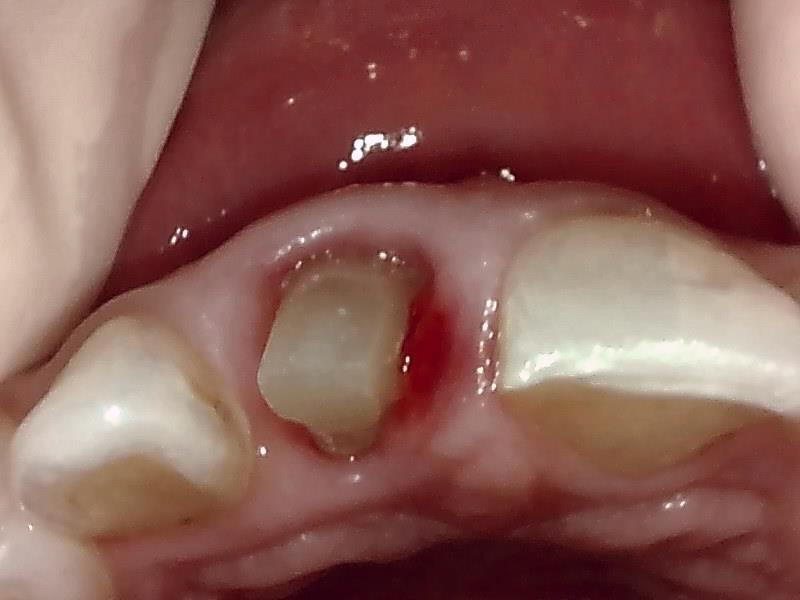

仮歯の装着して近心歯肉の回復を待つ。

仮歯の装着後、歯肉の治癒期間は後1~2週間後程度になる。